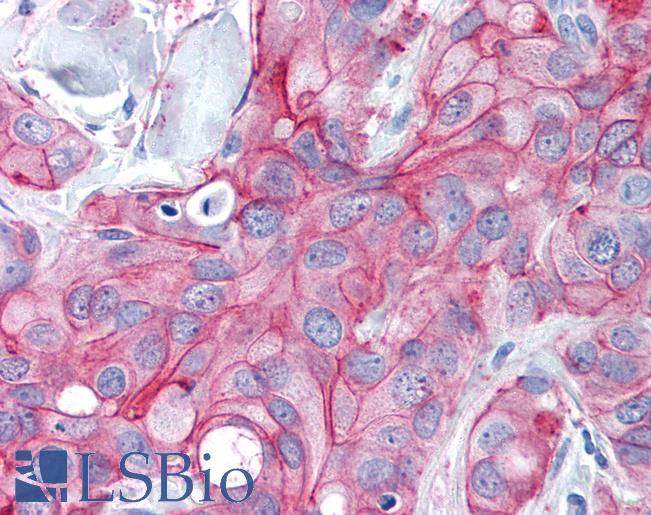

ERBB2 / HER2

Anti-ERBB2 / HER2 antibody IHC of human breast, carcinoma. Immunohistochemistry of formalin-fixed, paraffin-embedded tissue after heat-induced antigen retrieval. Antibody LS-B2133 concentration 5 ug/ml.